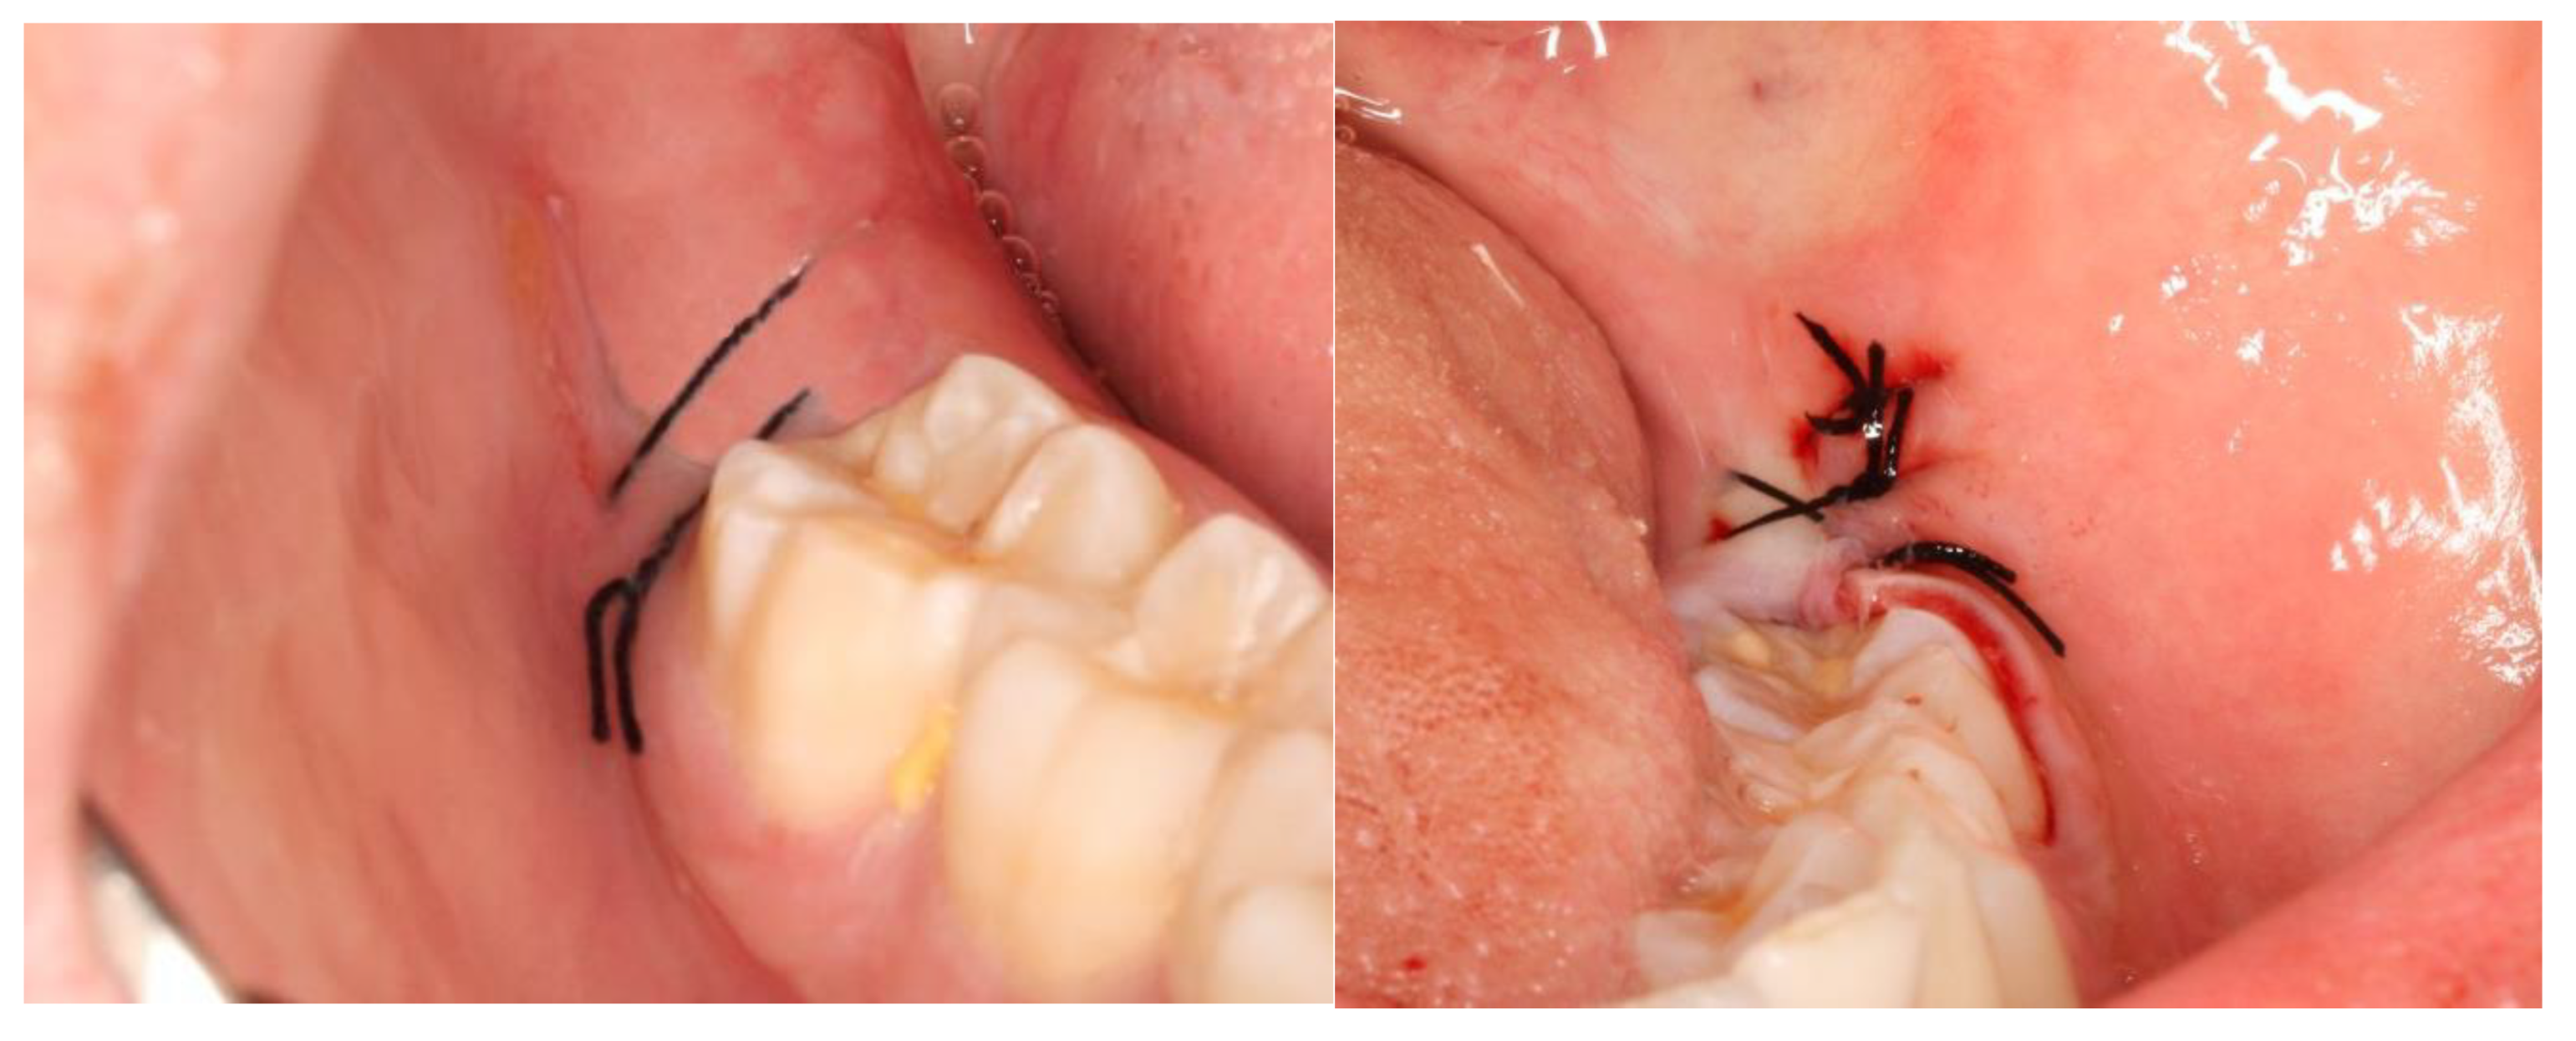

2.2. Definition of the Variables in Study and Follow-Up of Patients

3. Results